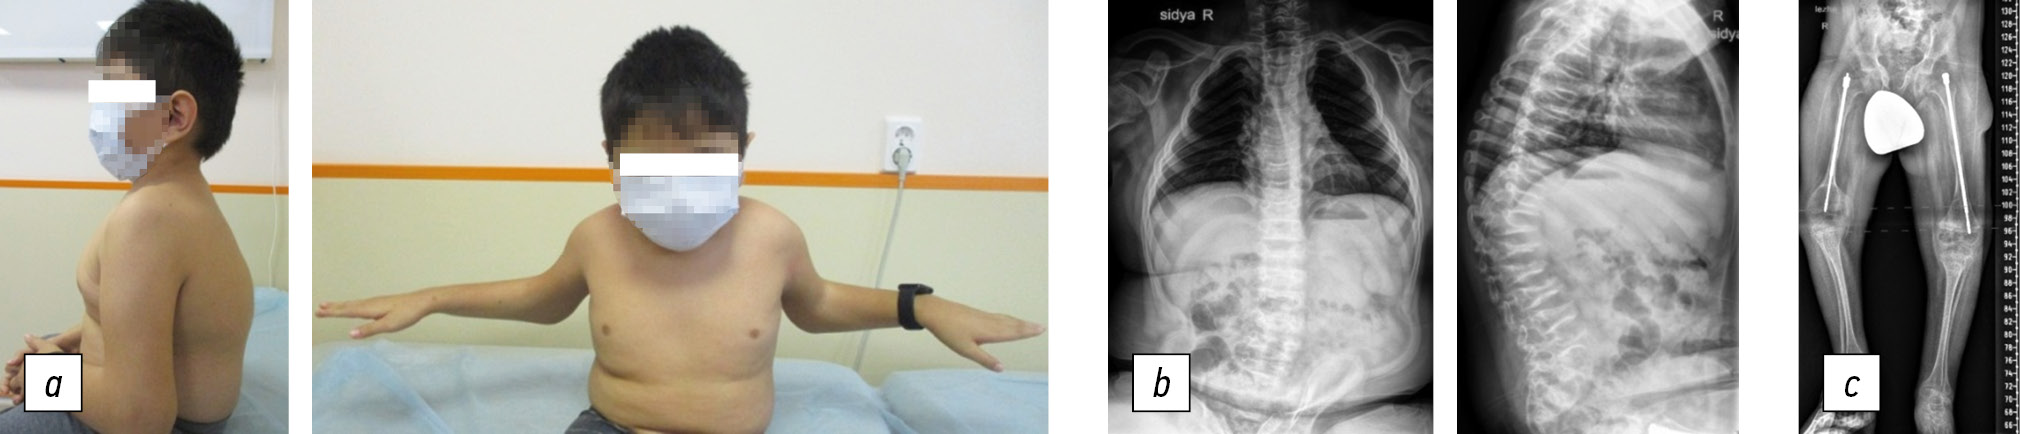

The boy is currently 10 years old and can sit independently but cannot walk. He has a height of 116 cm and a brachycephalic head. His face is symmetrical with protruding frontal tubercles, and his neck is short. The spinal axis is curved in the sagittal plane. Specifically, the cervical region is straight; local kyphosis in the thoracolumbar transition area and hyperlordosis in the lumbar region are noted. Additionally, a left-sided scoliotic deformity is determined in the thoracolumbar region. The length of the upper limbs is equal, and there are no limitations in the movements of the shoulder joints. There is a 40° flexion deficit in the right elbow joint and a 50° flexion deficit in the left elbow joint. Hand function is not impaired. The left lower limb is relatively short by 2.5 cm. Flexion contractures of the hip joints with a deficit of extension of 40° and flexion up to 60° on both sides were noted, as well as flexion contractures of the knee joints with a deficit of extension of 50° and flexion up to 80° on both sides. Additionally, an equinovalgus deformity of both feet was observed.

Radiographs of the spine in frontal and lateral projections revealed local pathologic kyphosis in the thoracic region of 45°, platyspondylia, wedge-shaped vertebral bodies, hyperlordosis in the lumbar region, and a left-sided scoliotic arch in the thoracolumbar region of 26° (Fig. 4). Table 2 presents the densitometry data. The observation period revealed pronounced vitamin D deficiency (level: 12 ng/mL; normal range: 30–80 ng/mL). Additionally, increased levels of C-terminal telopeptide (up to 2.6 ng/mL; normal: 1.63–1.94 ng/mL) and N-terminal propeptide (1037 ng/mL at the beginning of treatment; 649 ng/mL at present; normal: 388–571.6 ng/mL) persisted. However, all other indices of bone tissue metabolism, including calcium, phosphorus, alkaline phosphatase, osteocalcin, and parathormone, were within normal limits.

Fig. 4. Patient I, 10 years old, Bruck syndrome type 2: a, general view of the patient; b, anteroposterior and lateral projection radiographs of the spine: local pathologic kyphosis in the thoracic region, 45° with decreased height and wedge-shaped vertebral bodies, hyperlordosis in the lumbar region, and 26° left-sided scoliotic arch in the thoracolumbar region; c, panoramic radiograph of the lower extremities in the anteroposterior projection: intramedullary fixation of the femurs with telescopic rods